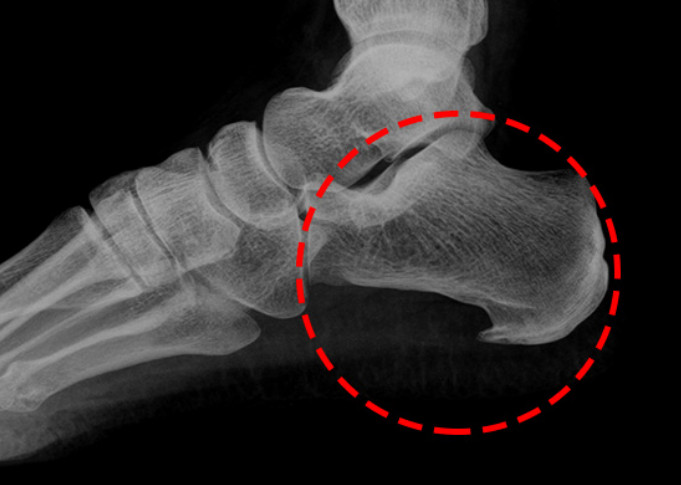

족저 근막염이란?

족저근막염은 발바닥 뒤꿈치에 염증이 생기면서 나타나는 통증을 말합니다. 남성보다 여성에게 약 2배 정도 더 많이 발생한다고 하며, 과도한 발의 스트레스나 무리한 운동이 주요 원인으로 알려져 있습니다. 이 밖에도 급격한 체중 증가나 평발 역시 발병 위험을 높이는 요인이 됩니다.

족저근막염 원인

무리한 걷기나 달리기

발에는 작은 근육이 많아 과도하게 사용하면 미세 손상이 발생합니다. 회복되지 않은 상태에서 다시 무리하면 염증이 생기고 통증으로 이어질 수 있습니다.